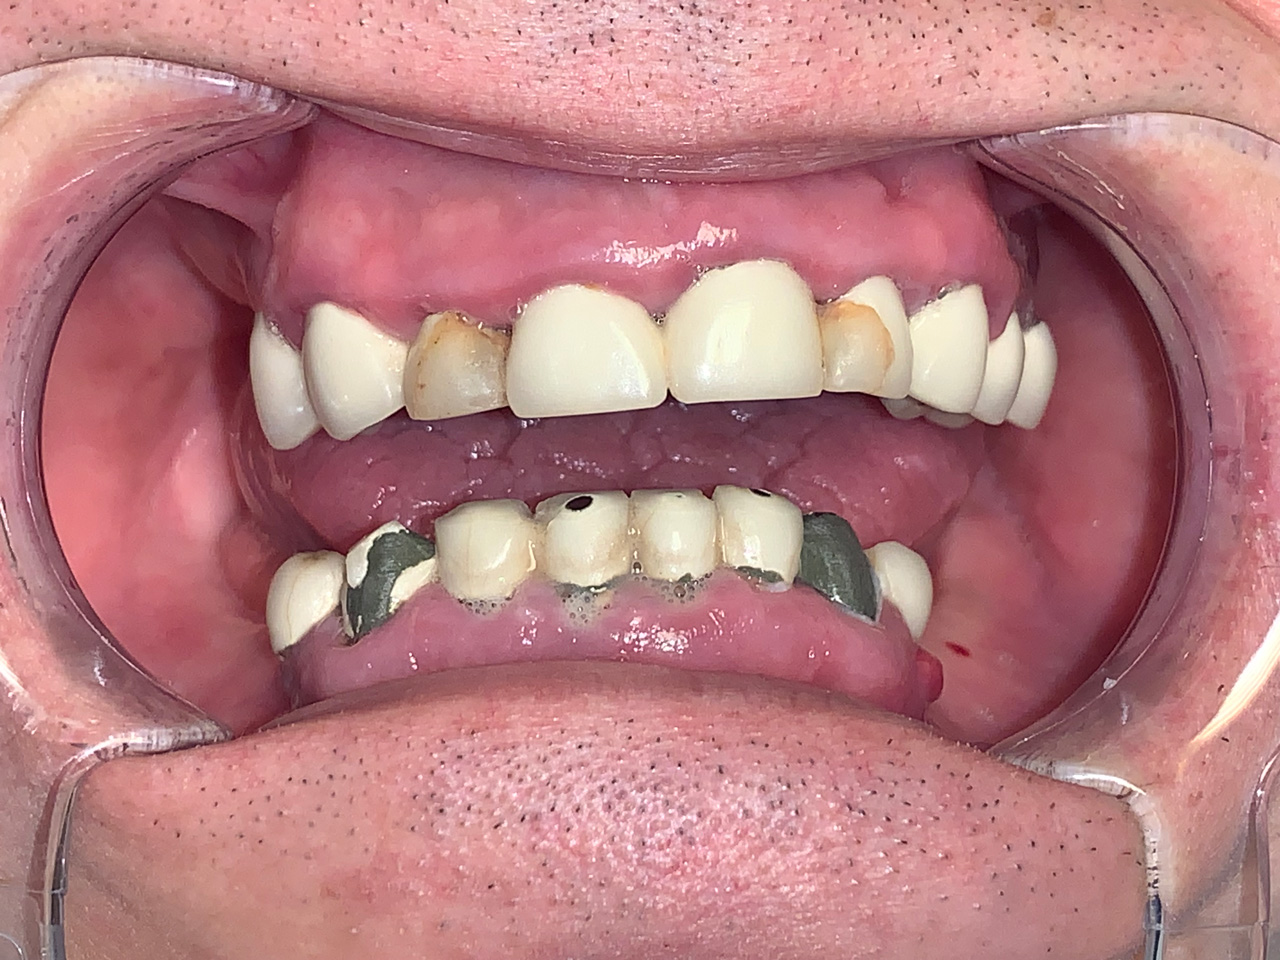

Elhanyagolt fogsor cseréje 2 nap alatt

2 nap alatt varázsoltuk ezt a szép esztétikus alsó, felső körhídat implantátumokkal megtámasztva a korábban elhanyagolt szájba. Az 1. nap 26 fogat távolítottunk el, mert annyira rossz állapotban voltak, és rögtön azonnal terhelhető IHDE svájci implantátumokat raktunk be, fentre 8, lentre 6 darabot. A sebeket összevarrtuk és intraorális szkennerrel digitális lenyomatot vettünk. 2 nap múlva pedig beragasztottuk a kész PMMA műanyag körhidakat. Dr. Kelemen Péter és a Symbion Fogtechnika munkája.